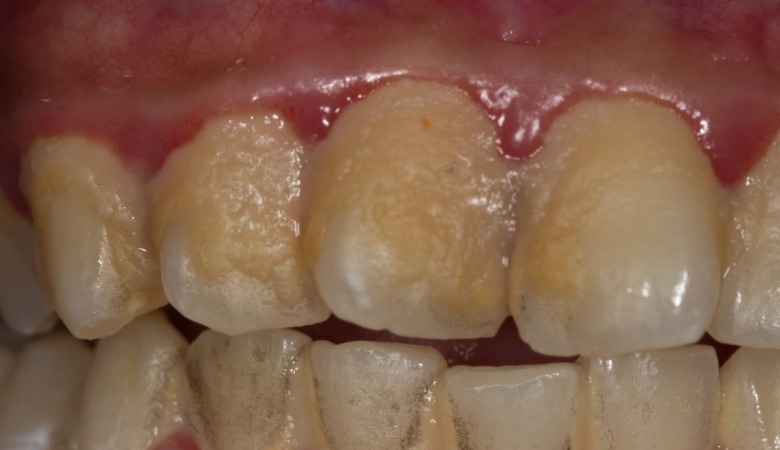

Cao răng không chỉ là vấn đề thẩm mỹ mà còn gây ra nhiều tác hại nghiêm trọng đối với sức khỏe răng miệng và thậm chí ảnh hưởng đến sức khỏe toàn thân nếu không được kiểm soát. Dưới đây là một số tác hại phổ biến của cao răng:

- Viêm nướu: Cao răng là nơi trú ngụ của vô số vi khuẩn, gây kích thích nướu, viêm nhiễm,… dẫn đến các triệu chứng như sưng đỏ, đau nhức và chảy máu chân răng, đặc biệt là khi đánh răng hoặc ăn nhai.

- Viêm nha chu: Đây một bệnh lý nghiêm trọng có thể gây tiêu xương, làm răng lung lay và cuối cùng là dẫn đến mất răng,… nguyên nhân chủ yếu là do tình trạng viêm nướu không được điều trị, vi khuẩn từ cao răng sẽ tiếp tục tấn công sâu hơn vào các mô nâng đỡ răng, bao gồm dây chằng nha chu và xương ổ răng.

- Hôi miệng: Cao răng chứa đựng nhiều vi khuẩn gây mùi khó chịu, điều này không chỉ khiến bệnh nhân mất tự tin trong giao tiếp mà còn là dấu hiệu của các vấn đề sức khỏe răng miệng khác.

- Mất thẩm mỹ: Cao răng khi đã sẫm màu, sẽ làm cho răng trông kém sạch sẽ và ảnh hưởng đến nụ cười và sự tự tin của mỗi người do các mảng cao răng lớn có thể nhìn thấy rõ ràng khi cười hoặc nói.

- Tụt nướu: Sự viêm nhiễm do cao răng gây ra có thể dẫn đến tình trạng nướu bị tụt xuống, làm lộ chân răng, khiến cho bệnh nhân dễ bị nhạy cảm với nhiệt độ và thức ăn, gây ê buốt răng khi ăn nhai.

Cao răng không được xử lý có thể gây viêm nướu, viêm nha chu hoặc dẫn đến mất răng vĩnh viễn (Nguồn: Internet)